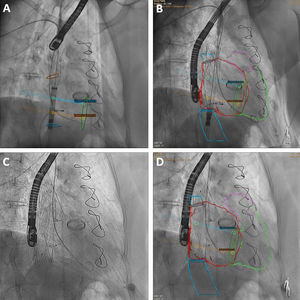

Nuestro grupo ha explorado el papel de la fusión TC-fluoroscopia (HeartNavigator 3.0, Philips, Países Bajos) en 6 pacientes consecutivos (Tricentro 2, TricValve 4), con colocación de marcadores específicos (Tricentro: desembocadura de las cavas y orientación de la neoválvula; figura 2A,B; TricValve: mismas medidas y alturas que el cribado; figura 1D,E). En nuestra experiencia, fue un complemento preciso: mejoró la comprensión anatómica, permitió posicionar el arco de fluoroscopia ortogonal a la zona objetivo, retirar el catéter pig-tail antes del despliegue, con lo que se evita enjaularlo y se mantienen las referencias o se detecta un inadvertido mal posicionamiento del catéter en la rama pulmonar (delimita los bordes y el volumen de la arteria, mientras que el catéter puede posicionarse en aspecto superior o inferior y puede disminuir la precisión del implante). También podría reducir las angiografías selectivas y el material de referencia utilizado, aunque esto no fue objeto de análisis en nuestra experiencia inicial. El resultado final comparado se observa en la figura 1C,F y la figura 2C,D.